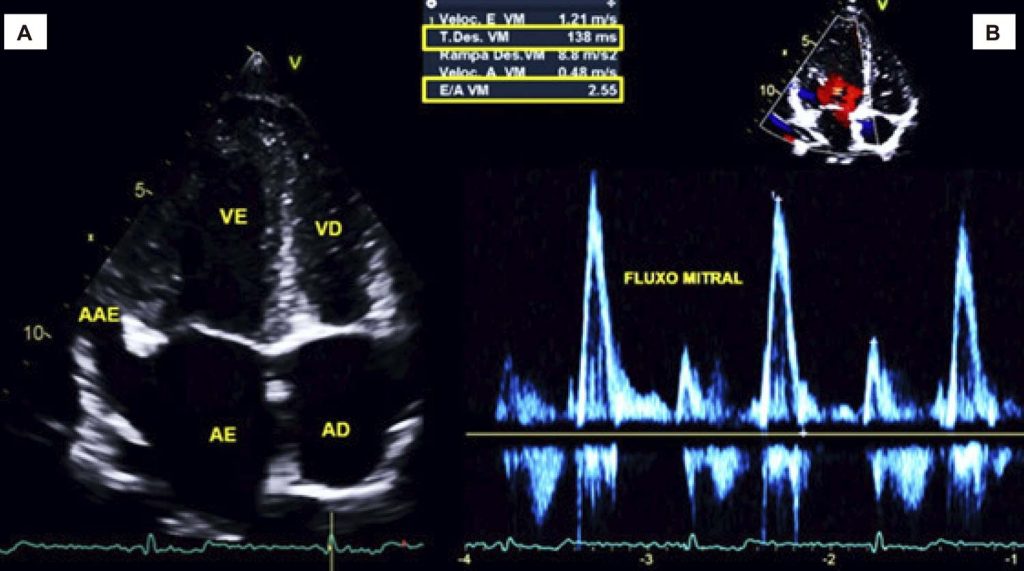

Como sempre acontece na medicina, toda vez que temos alguma mudança de paradigma, ou uma nova entidade clínica é descoberta, passamos inicialmente por uma fase de exagero no diagnóstico seguida por uma fase de descrédito para finalmente atingirmos o equilíbrio com a maturidade e o conhecimento adquirido com o tempo. Foi assim com o prolapso da valva mitral, que apresentava incidência de mais de 35% em mulheres jovens no início dos anos 1970 e que hoje sabemos ser de aproximadamente 2,4% sem diferença entre os sexos. O mesmo ocorreu com o diagnóstico de não-compactação ventricular e diversas outras entidades clínicas e, porque não dizer, com o diagnóstico de disfunção diastólica. Quantos idosos absolutamente saudáveis não foram diagnosticados com disfunção diastólica leve (grau I) por apresentar apenas inversão da relação E/A no fluxo mitral ao Doppler? Almeida et al., verificaram o impacto da utilização da diretriz de 2009 em relação à de 2016 no diagnóstico de disfunção diastólica nessa população (1000 indivíduos com mais de 45 anos) e encontraram apenas 1,4% de disfunção diastólica onde haveria 38,2% usando a diretriz anterior.